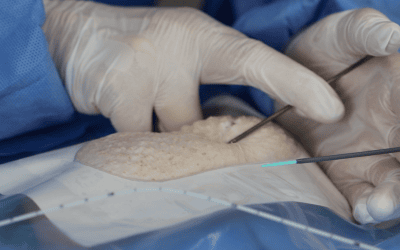

Los PICC de doble y triple luz (Figura 2) se asocian con un aumento de las oclusiones. Dependiendo de la situación clínica, deben preferirse los lúmenes individuales tal y como apuntan las guías de práctica clínica16-19

La evidencia científica que ha estudiado las complicaciones relacionadas con el PICC, deja claro que el número de lúmenes SÍ importa y es un factor determinante en el posible desarrollo de complicaciones posteriores.El tamaño del catéter (Fr) debe ser el menor posible que permita administrar sin problemas el tratamiento pautado, acorde a:

A mayor número de lúmenes mayor número de complicaciones como infección, oclusión y trombosis16 y más rigurosos debemos de ser a la hora de asegurar la permeabilidad del catéter, tratando y manejando cada luz individualmente24.